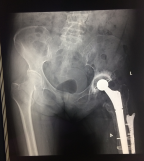

病例2 患者譚某,女性,79歲,左髖關(guān)節(jié)行置換手術(shù)14年,行翻修手術(shù)8年,兩小時(shí)前摔傷致左髖關(guān)節(jié)翻修術(shù)后假體周圍骨折,到我院住院治療,專家團(tuán)隊(duì)討論后,決定進(jìn)行二次翻修手術(shù),二次翻修相比第一次翻修,手術(shù)難度更大,面臨的困難更多,經(jīng)過精心的術(shù)前設(shè)計(jì),周密的術(shù)前準(zhǔn)備,手術(shù)過程順利,術(shù)后效果良好。

術(shù)前X線片

術(shù)后X線片